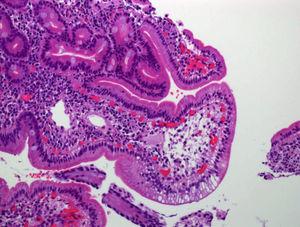

Figura 2. Anatomía patológica en caso clínico 2: dilataciones linfáticas en punta de vellosidad con enterocitos cargados de material lipídico.

El diagnóstico en el primer caso clínico fue sencillo; la clínica y las dilataciones linfáticas patognomónicas lo confirmaron. El segundo caso precisó una mayor serie de pruebas, debido a que las muestras histológicas se informaron como inespecíficas, a pesar de observarse mínimas dilataciones linfáticas. Inicialmente se planteó como diagnóstico más probable una LIS a infección por VVZ. Hay escasos casos publicados de varicela y EPP secundaria a la afectación del tracto gastrointestinal por VVZ7. Ross et al8 publicaron el caso de una mujer de 46 años con varicela grave y LIS, pero no hemos encontrado ningún caso pediátrico. Después de la segunda FEGD, ante la firme sospecha de LIP se revisa la histología, en la que se aprecian (de forma sutil) dilataciones linfáticas en la parte apical de la vellosidad y enterocitos cargados de grasa en las últimas muestras (fig. 2).